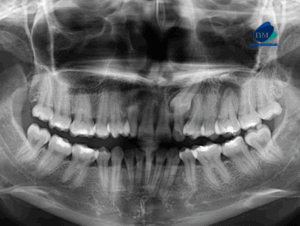

Paciente femenina acude a la sede de IDM- Miraflores para una tomografía computarizada para la evaluación de terceras molares. A la evaluación de la radiografía